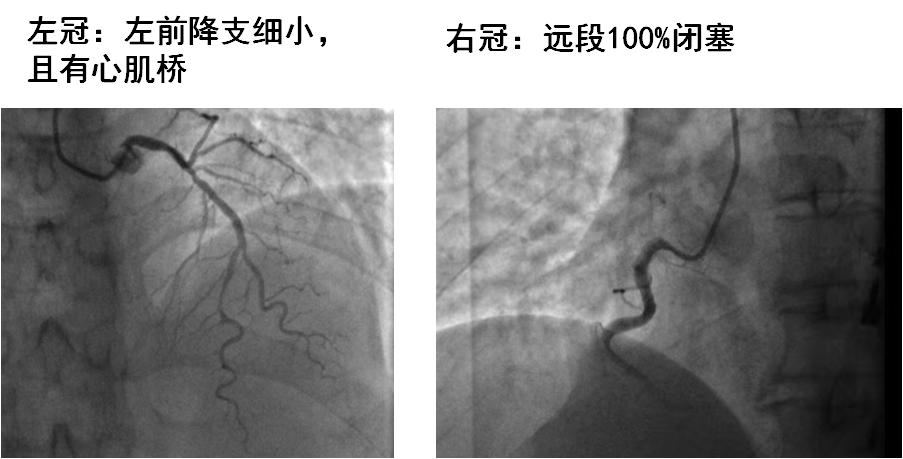

09.03入院

09.04